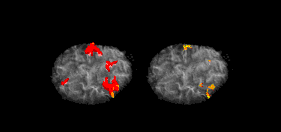

Cognitive neuroscience aims to reduce cognition to its neural basis using new technologies such as fMRI, repetitive transcranial magnetic stimulation (rTMS) and Magnetoencephalography (MEG) as well as older methods such as Positron emission tomography (PET) and Electroencephalography (EEG) studies. Due to the correlational designs used in fMRI, many scientists have coined this up and coming field as the new phrenology in the sense that techniques such as fMRI rely heavily on complex statistics.[17] Type 1 errors can lead scientists to draw premature and incorrect causal relationships if improper designs are used.[18]

An assessment of visual-spatial memory involves mimicking a researcher as he/she taps nine identical spatially separated blocks. The sequence starts out simple, usually using two blocks, but becomes more complex until the subject's performance suffers. This number is known as the Corsi Span, and averages about 5 for normal human subjects. An fMRI study involving subjects undergoing this test revealed that while the sequence length increases, general brain activity remains the same.[19] So while humans may show encoding difficulty, this is not related to overall brain activation. Whether able to perform the task well or not the ventrolateral prefrontal cortex is highly involved. Corsi blocks tasks with a normal forward order requires support from the visuospatial sketch pad, but not from the phonological loop. When the sequence to be recalled becomes longer than three or four items, central executive resources are used[20]